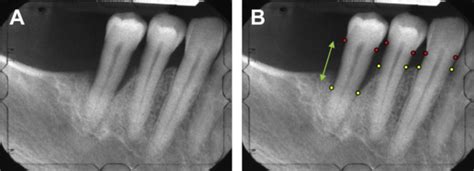

Radiografía mostrando pérdida ósea por periodontitis

El diagnóstico se hace con una sonda milimetrada: sondaje. En éste caso, la encía tiene un aspecto normal. Sin embargo estamos ante una Periodontitis entre moderada a grave. La sonda penetra en la encía unos 7 mm. eso indica pérdida ósea. En un caso de salud, la sonda marca desde cero mm a 1.5 mm

El diagnóstico se hace con una sonda milimetrada: sondaje.

- En la Periodontitis leve, la sonda penetra en el surco gingival de 3 a 4 mm. aproximadamente.

- En la Periodontitis moderada la sonda penetra de 5 a 6 mm.aproximadamente.

- En la Periodontitis grave, la sonda penetra más 7 mm. Si las raíces son cortas, sondajes menores ya son graves. En el caso del molar con dos raíces, la enfermedad invadió la bifurcación.